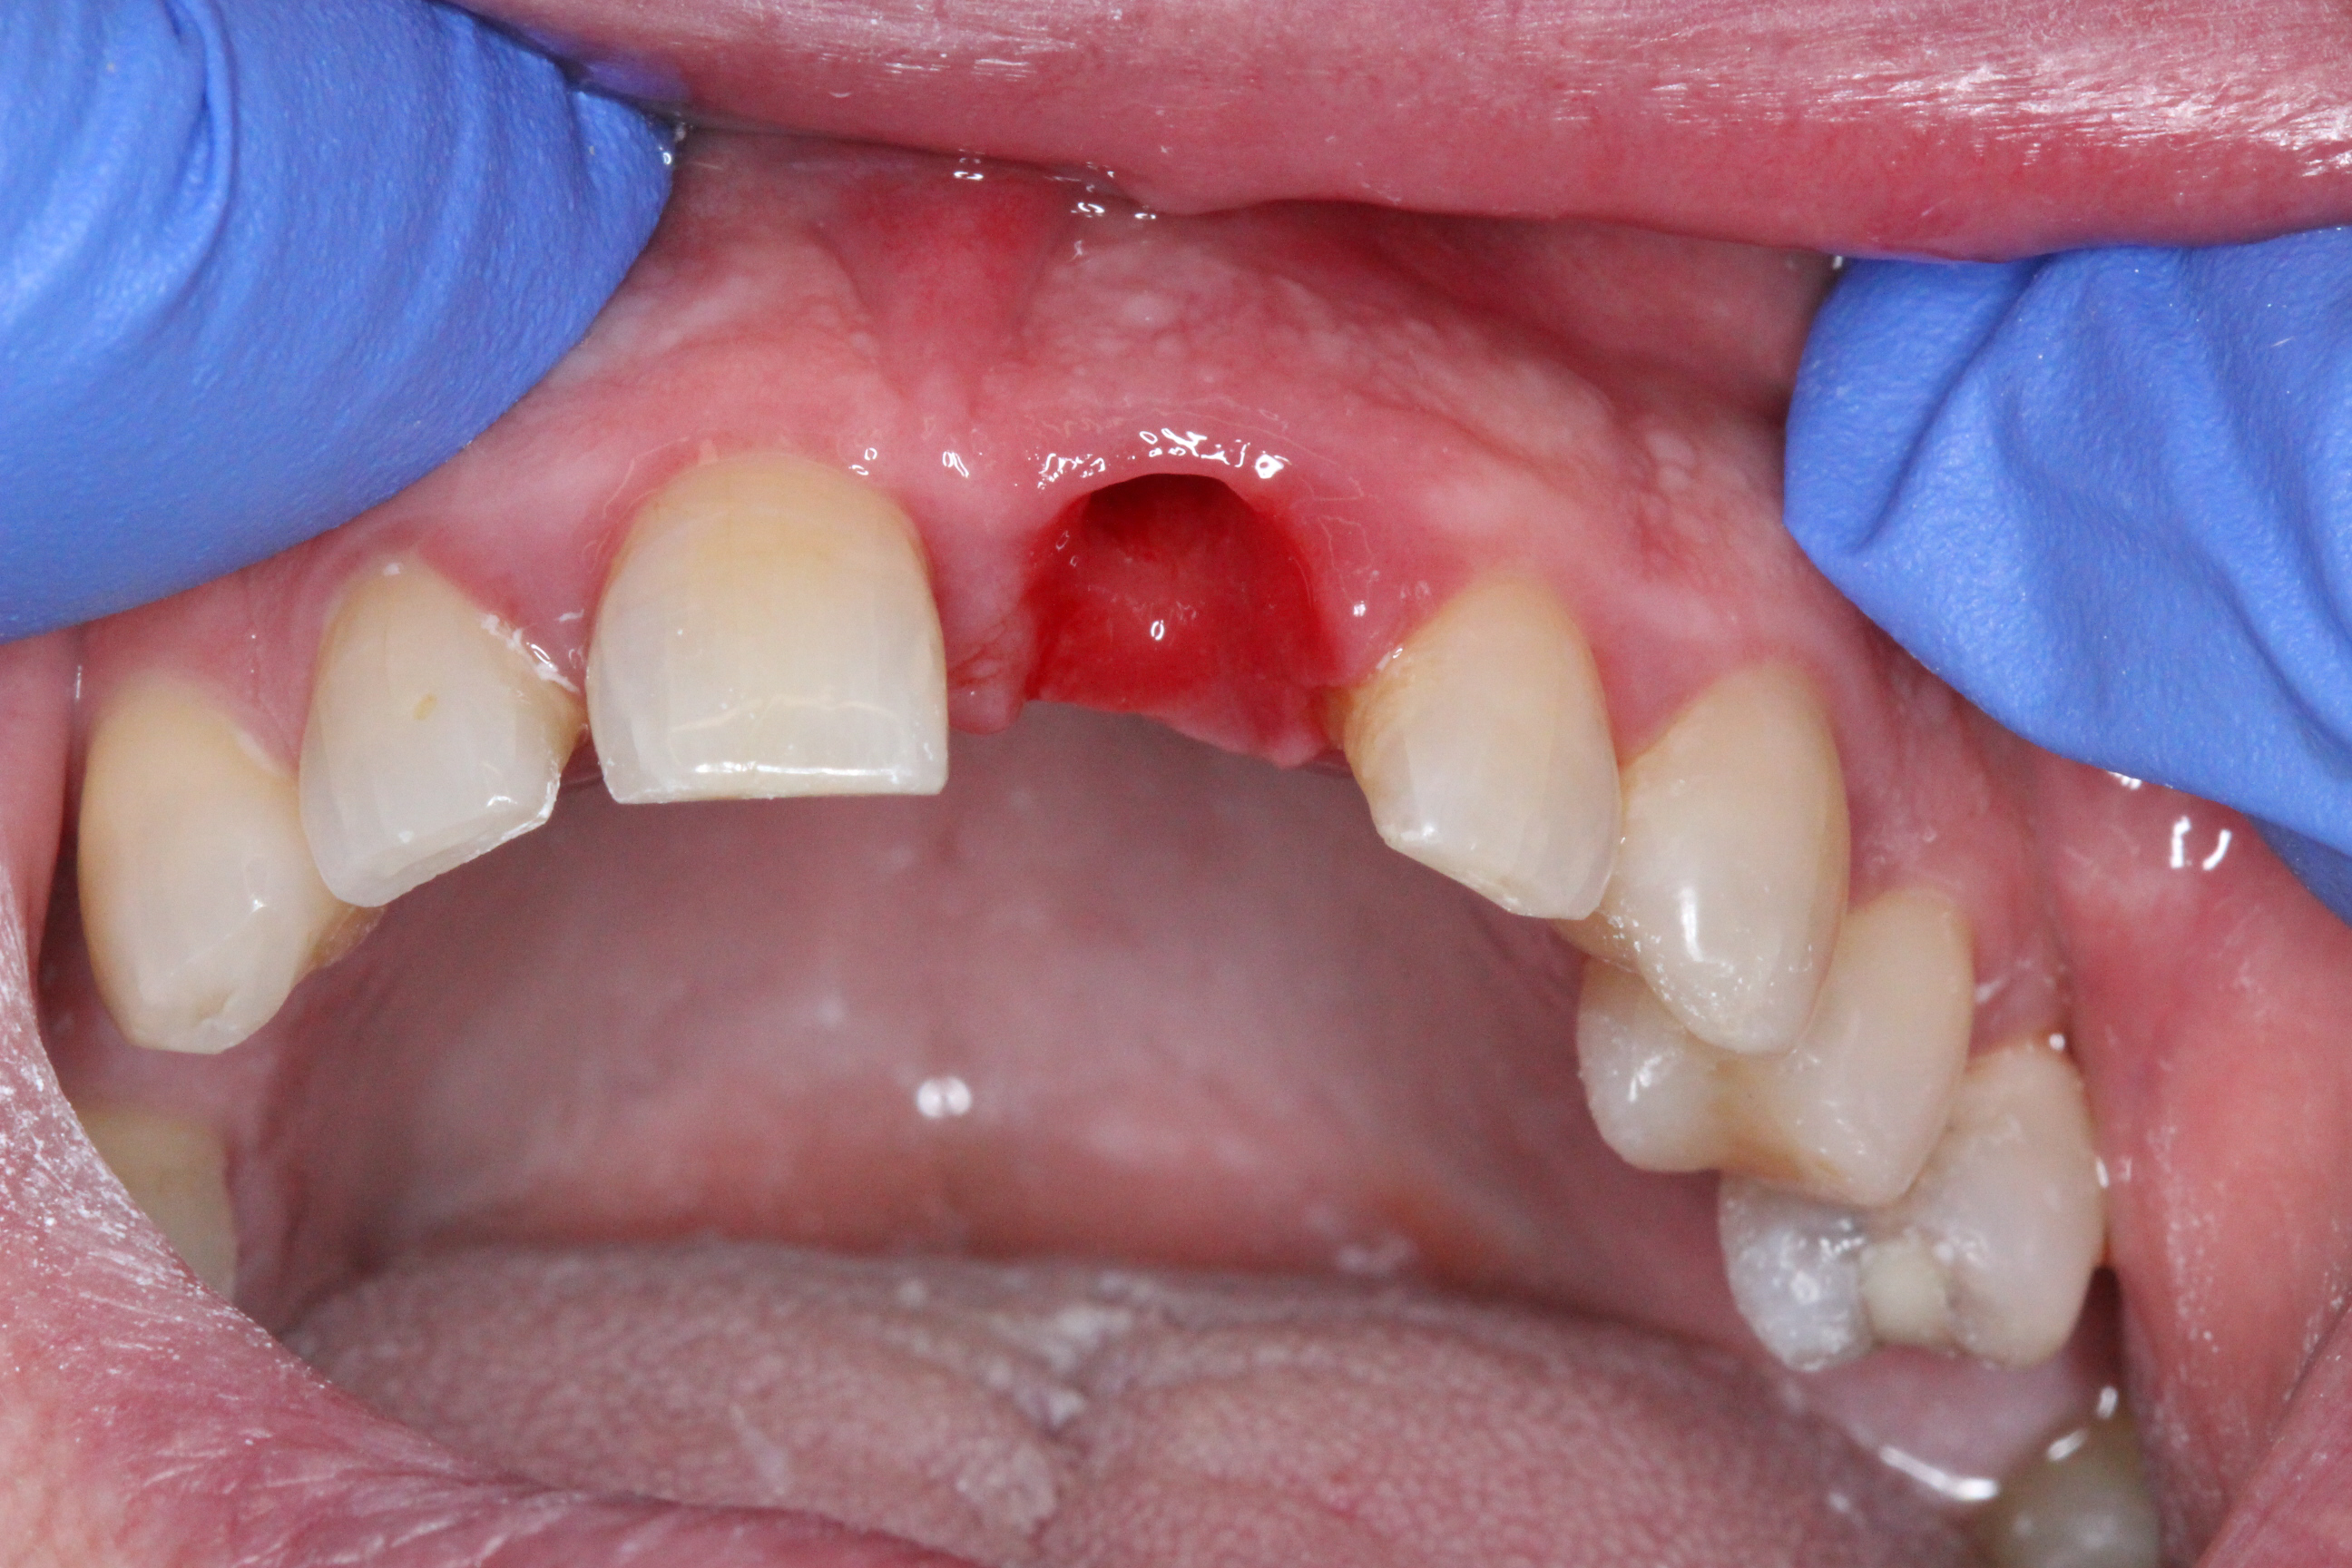

An atraumatic extraction of tooth 21 was performed without flap elevation in order topreserve the soft tissue architecture.

The DICOMLAB surgical guide was positioned, and the implant was placed according to the digital plan.

Implant placed: DSI Conical Implant – 4.3 × 13 mm.

Primary stability achieved: 45 Ncm insertion torque.

Achieving this level of stability and ideal prosthetic positioning would have been extremely difficult without guided surgery due to the severe buccal bone deficiency.